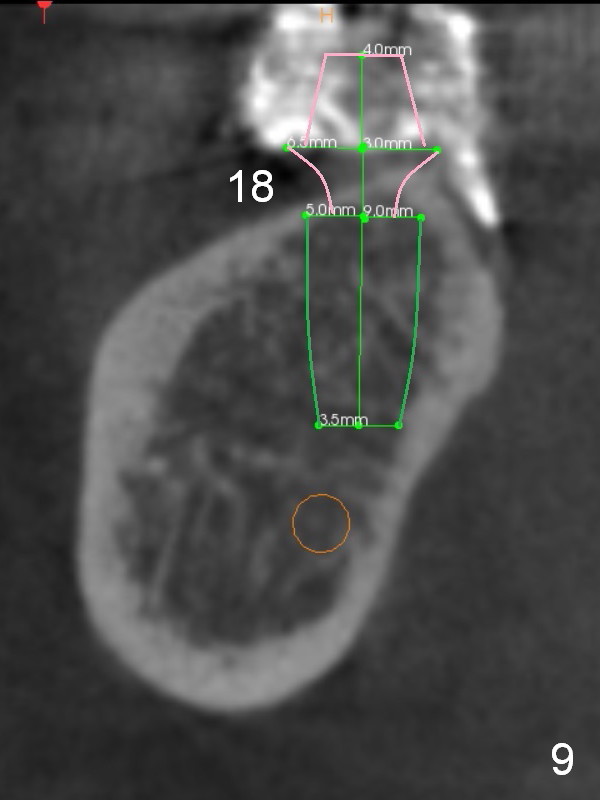

A 73-year-old woman requests implant restoration at #18 and 19 (Fig.1). The left posterior occlusion is Class II (Fig.1,2). The right one is Class I because of small dimension of the restoration at #30 (Fig.3 (premolar)). The normal size of the lower left molars will keep Class II occlusion (Fig.4), which may create cheek bite posteriorly. To correct the occlusion to Class I, move osteotomies to the mesial aspect of waxed-up molars (Fig.6 white circles). Finally a premolar crown and the 1st molar will be placed at #19 and 18, respectively. The supraerupted opposing molars (Fig.5 arrowheads) will to be adjusted when the abutments are placed at the lower molars.

The lady has taken Fosamax for osteoporosis several years. The medicine may cause osteonecrosis. CBCT study does not show sign of osteonecrosis apparently (Fig.7-9). Since the ridge at #19 is narrow (Fig.8), it is reasonable to have a premolar there after ridge trimming.